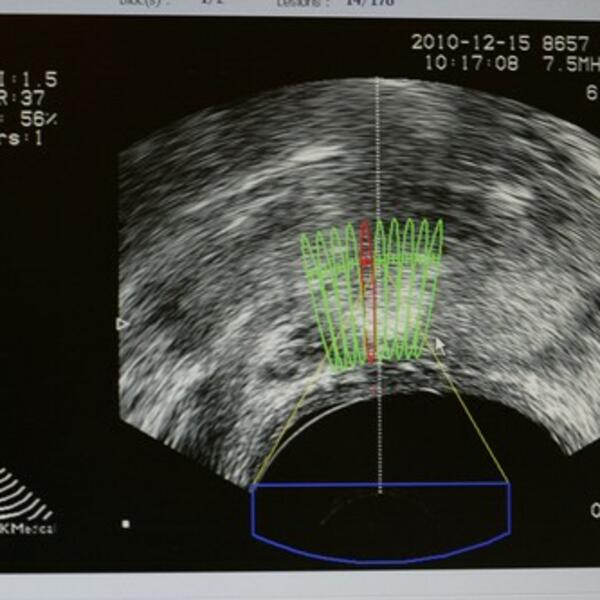

"Moram da kažem da tokom prethodne godine 460 biopsija je urađeno samo u našem polikliničkom delu i nažalost, od toga 380 je dokazanih karcinoma prostate. Beleži se jedan značajan porast uopšte sa malignim bolestima, takođe, karcinom bubrega kojim se bavimo poslednjih nekoliko godina intenzivno, u metastatskoj fazi je sve više prisutan i to kod mlađe populacije".